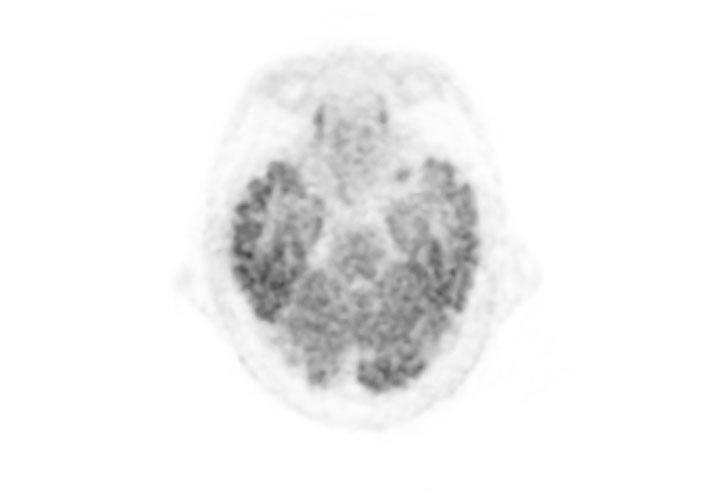

Fusion image of PET and MRI

- Imaging protocol

- Injected dose: 2.87 MBq/kg, 18F-FDG

- Uptake time: 42 minutes

- Scan time: 30 minutes